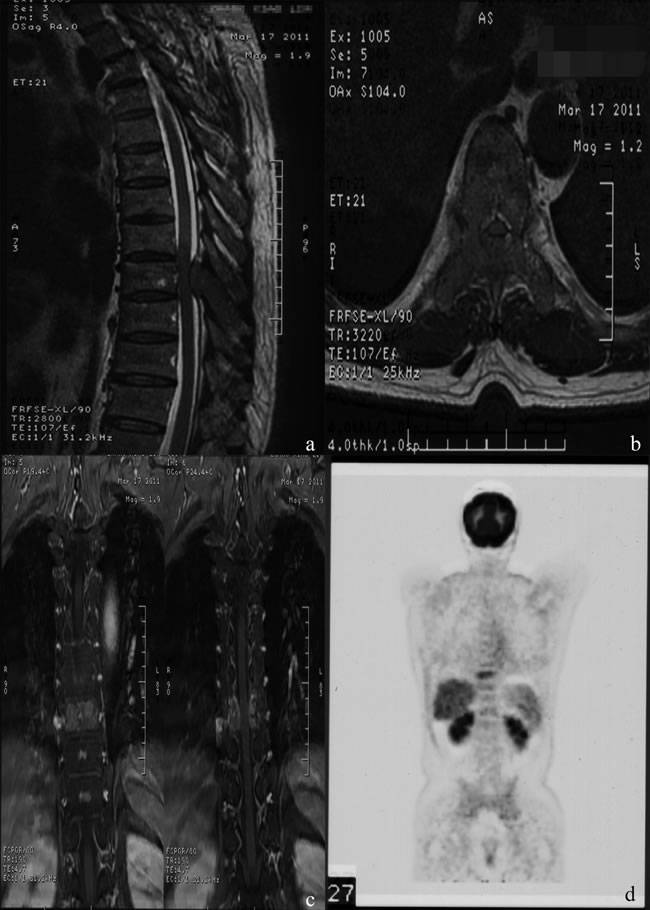

HCC is the second leading cause of cancer-related death in China and the third worldwide [24, 25]. Because of improved diagnosis and therapeutic modalities for primary HCC, more cases of extrahepatic metastases, especially bone metastasis, have been detected in recent years. MSCC from primary HCC can be seen as a certain probability in clinical practice and remains a challenge for clinicians. In patients with the terminal stage of advanced cancer associated with persistent pain and neurological defects, surgical intervention could be an effective way to relieve symptoms directly and enhance the quality of life. Figure 3 and 4 illustrate the preoperative radiologic findings and postoperative condition (54 months after spine surgery) of a representative patient who ever underwent excision of primary HCC and metastatic lesion. And he experienced PFS during a final follow-up of 59.0 months, with a satisfactory quality of life after surgery and adjuvant therapies.

Figure 3: A.-D. Typical MRI and PET-CT images , showing abnormal signal of T9 body and appendix with spinal canal stenosis and spinal cord compression, abnormal 18F-fluorocholine uptake of the thoracic vertebrae.